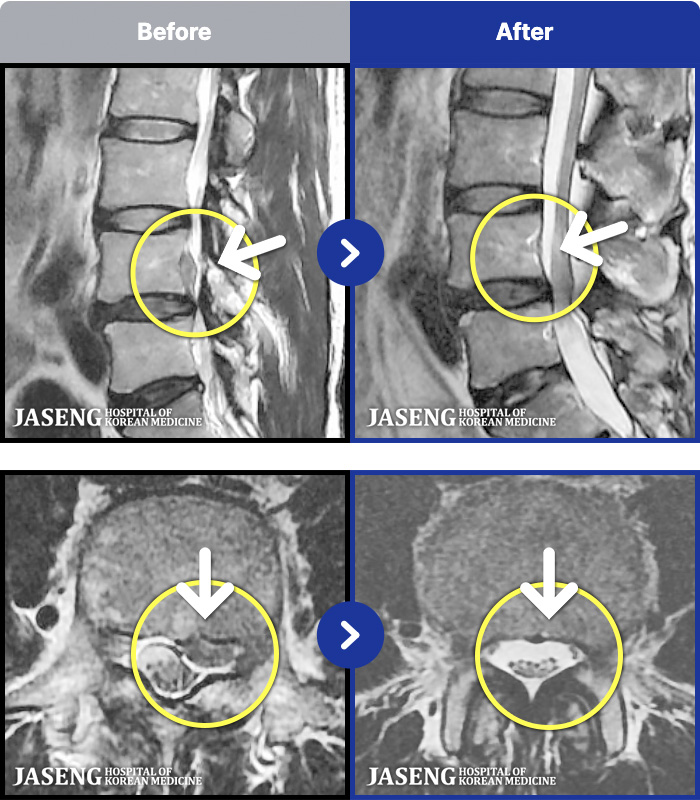

54 MRI ũ ʸ Ȯϼ.

[뱸] 19.11.28~25.05.06